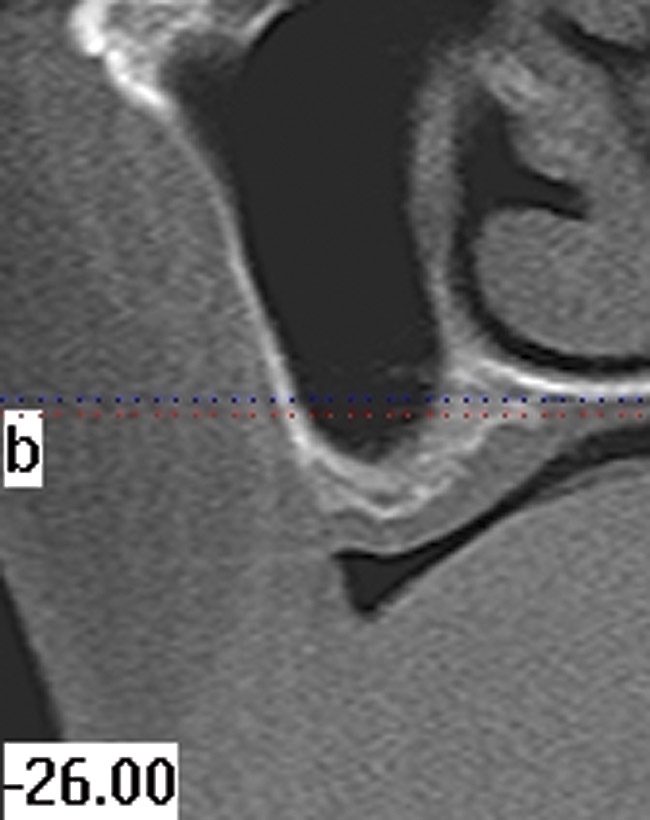

As mentioned, all risk factors associated with both root canal and implant therapy must be carefully considered. Comprehensive clinical and radiographic assessments are necessary to evaluate the patient's risk factors associated with his or her particular case (Figure 1, Figure 2 and Figure 3). The primary risk factors for implants can include smoking, bone quality, and systemic health. For endodontic therapy the primary risk factors are related to the anatomic root complexity, failed root canal treatment with significant technical defects manifested as iatrogenic events, less-than-optimal periodontal status of the tooth (due to a subsequent risk of vertical fracture), and a clinician's lack of experience with regard to the case's complexity. A strong correlation exists between failed root canal treatment and a lack of coronal seal after treatment. This is highly relevant in treatment planning. Often, endodontically treated teeth fail not because they were treated inappropriately and need extraction, but rather, because they have been left unsealed and assaulted by bacteria after the endodontic therapy, causing subsequent long-term clinical failure (Figure 4 and Figure 5).

The use of cone-beam computed tomography (CBCT) has revolutionized clinical diagnostic abilities. Featuring advantages such as a relatively small size, less radiation exposure, and lower cost, CBCT has gained popularity by improving predictability and the quality of care in implant dentistry. This technology has value in aiding in the diagnosis of root fractures. Recently, a study found dental CBCT exhibited greater accuracy (62.8% versus 54.5%) in helping to diagnose vertical root fractures than conventional radiography. The investigators concluded that use of dental CBCT is effective for the diagnosis of root fractures regardless of the direction.3

While not elaborated on here, it is noteworthy that there are a number of additional treatments for resorption that have been suggested in the literature, including calcitonin,27 Emdogain,24,28 and Alendronate (third-generation bisphosphonate in treating EIRR)29 (Figure 6, Figure 7, Figure 8, Figure 9, Figure 10, Figure 11, Figure 12, Figure 13, Figure 14 and Figure 15).